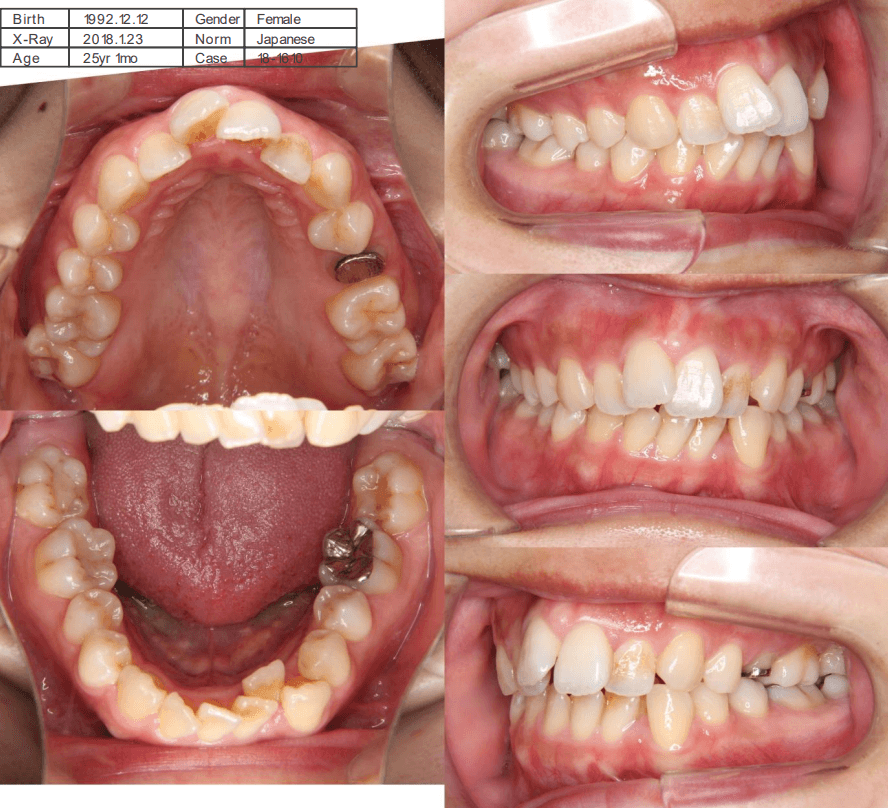

| 年齢・性別 | 25歳女性 |

|---|---|

| 主訴 | 前歯の歯並びの乱れ(叢生)を気にされて来院された25歳女性。咬み合わせや審美的な改善を希望されていました。 |

| 治療期間・回数 | 4年5ヶ月・30回 |

| 費用 | 1100,000円(税別) |